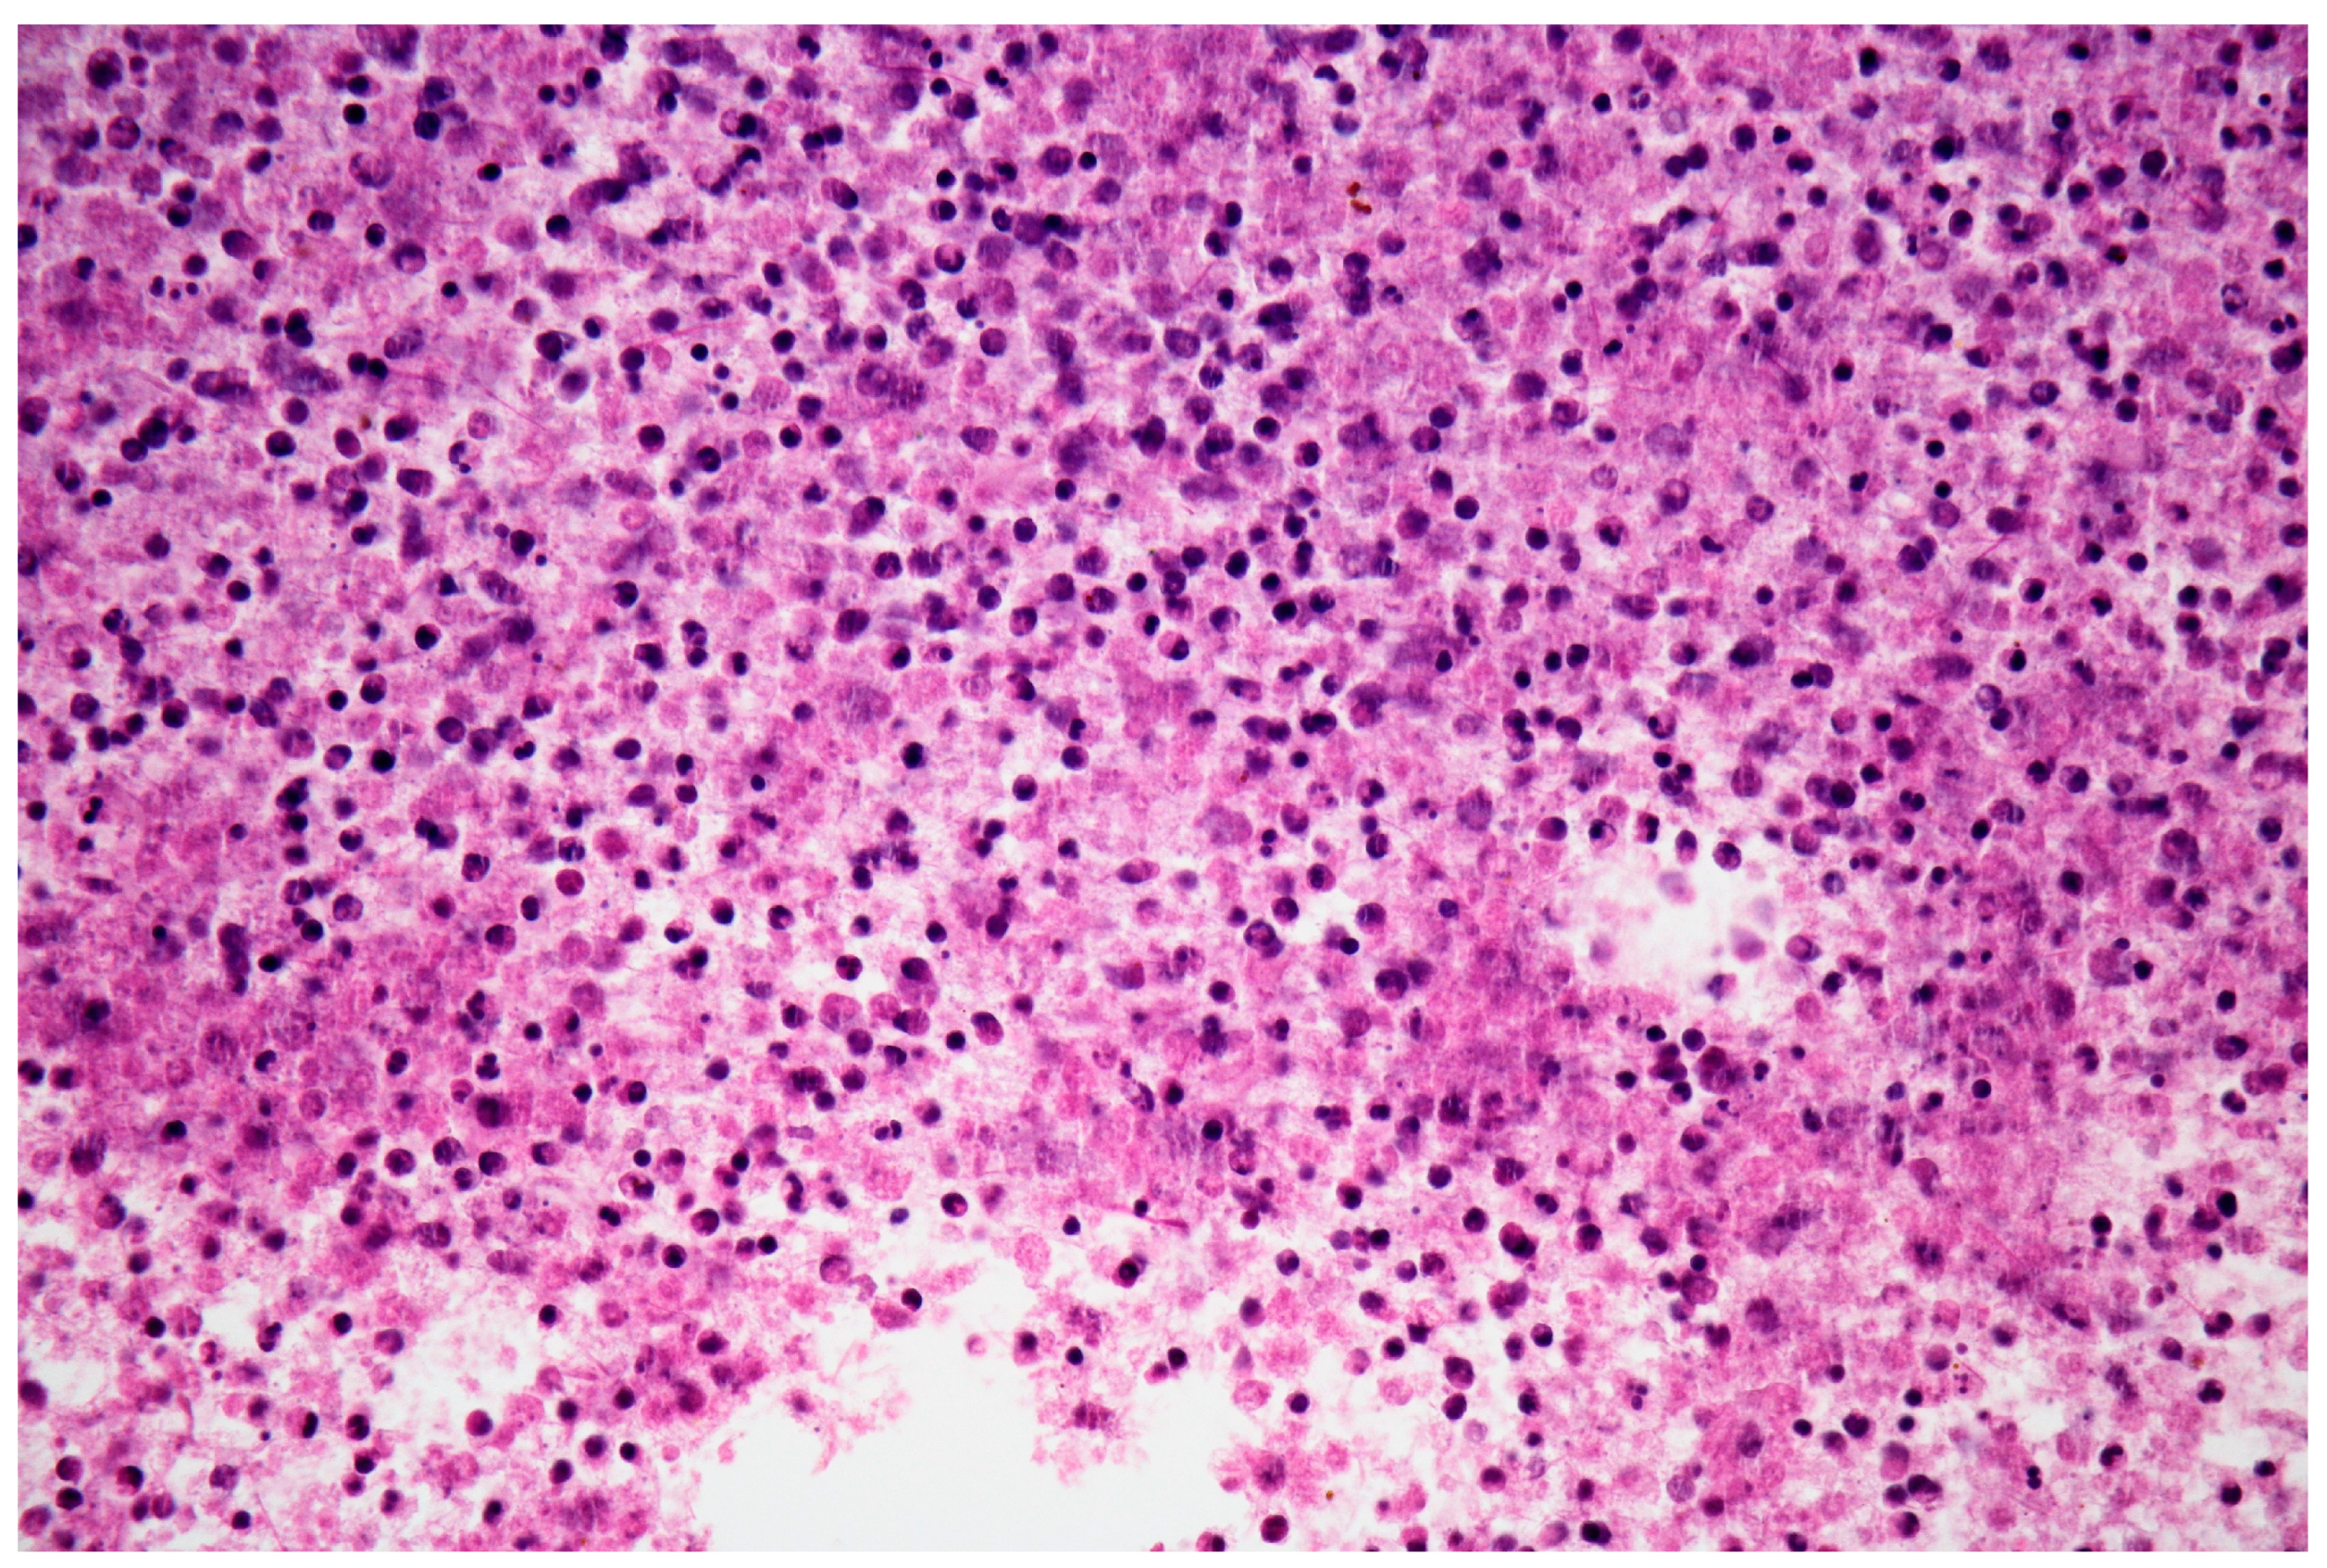

2. Case Presentation